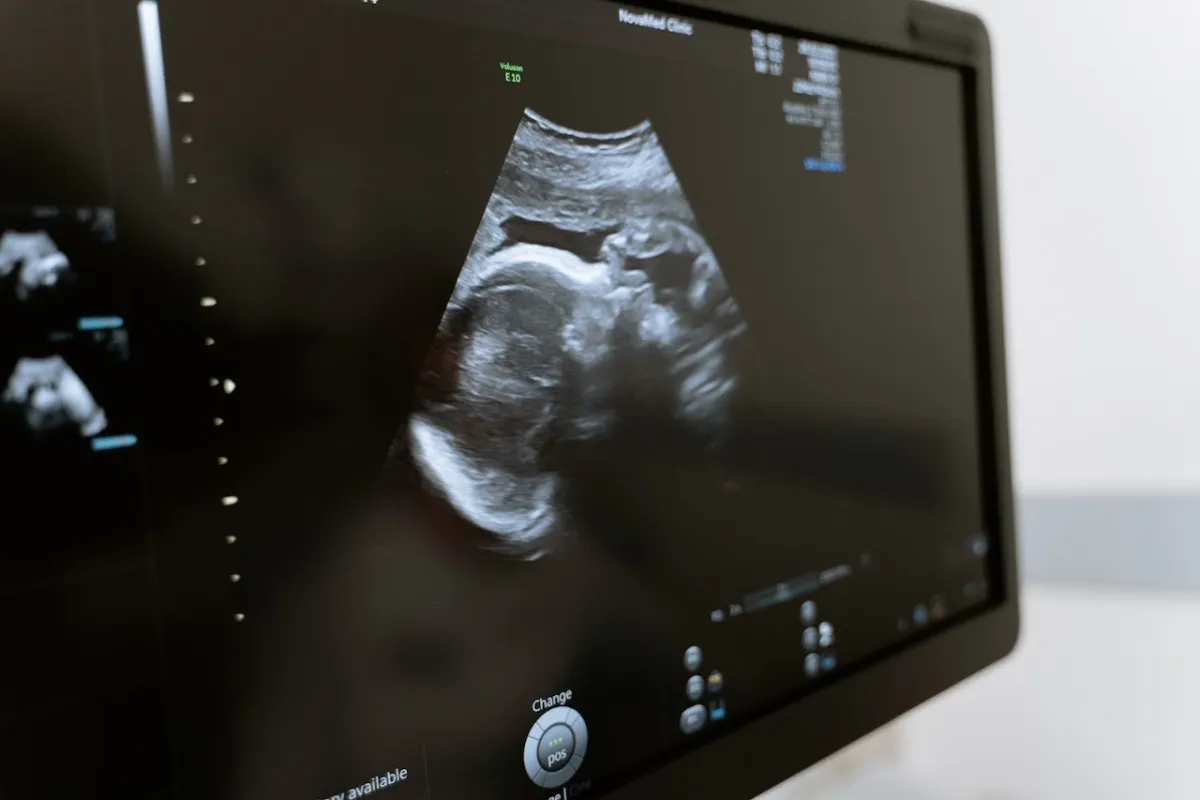

فحص بالأمواج فوق الصوتية للتحقق من موقع حدوث الحمل.

العلامات، هي ذاتها علامات الحمل الطبيعي التي قد تختبرينها في الثلث الأول من الحمل . لكن قد لا تمر بعض النساء بأي أعراضٍ على الإطلاق في هذا النوع من الحمل. لكن في حال وجود أعراض، فعلى الأرجح أنّك ستلاحظين علامات الحمل خارج الرحم بين الأسبوع الرابع والأسبوع الثاني عشر من الحمل . والطبيب وحده في بعض الحالات هو أول من يلاحظ علامات الحمل خارج الرحم، وذلك أثناء إجراء فحص الحمل بالأمواج فوق الصوتية لأول مرة.